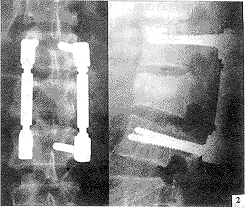

, http://www.100md.com 3.2.1 骨折椎平面 间接减压效果T12、L1骨折优于L2骨折。这可能与T12、 L1正常生理状态下有轻度后凸,在恢复脊柱前凸过程中,后纵韧带及椎间盘纤维环张力较大,使骨块复位应力增强,而L2是后凸与腰椎前凸过渡椎,纵向韧带张应力增大不明显有关。根据间接复位能力不同这一特点,后期我们对L2骨折术前存在严重椎管入侵(>50%)者,在实施复位固定同时,作经椎弓根侧前方减压,使术后椎管腔达到足够的减压范围,见图1~3。

图2 L2爆裂型骨折术后X线片